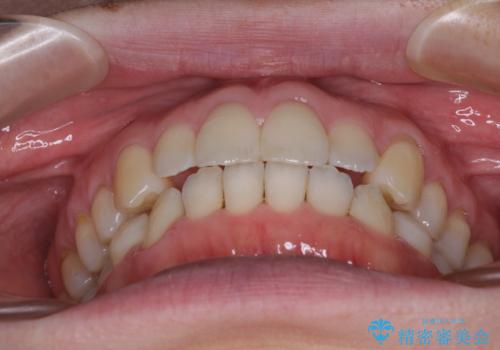

インビザラインによる矯正治療は、受け口傾向の治療に非常に適した方法であり、事前にシミュレーションに沿って治療を進めることできます。

今回の治療では骨格的な偏位があったためアンカースクリューを使用し、より確率の高い治療を行うことができました。